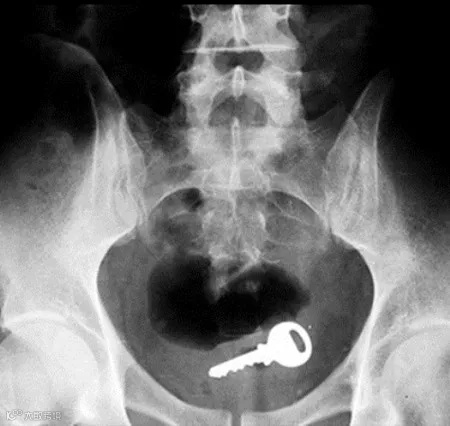

钥匙▽